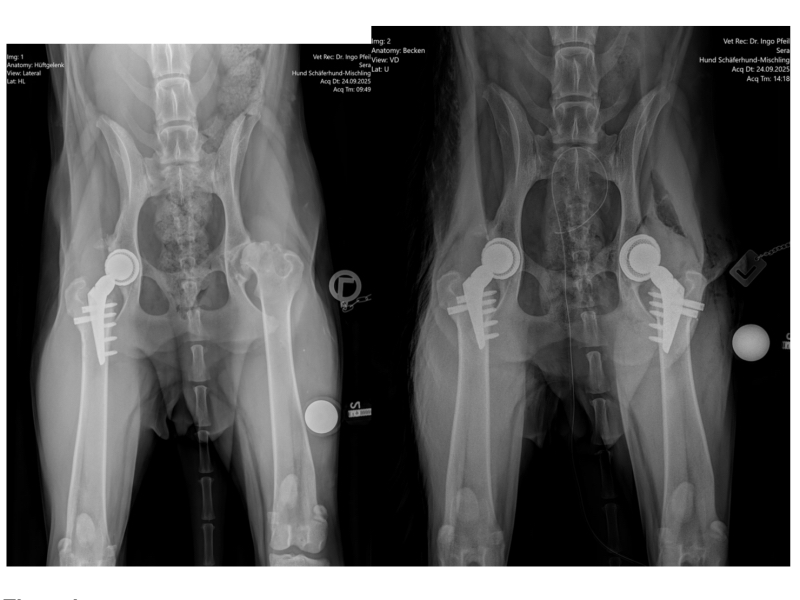

Ende September fuhr unser „Gnadenhof Taxi“ dann wieder einmal in Richtung Dresden. Dieses mal allerdings gleich mit zwei Hunden im Gepäck, denn auch unser neuster Bewohner, Labrador Monte, sollte unters Messer. Sera und Monte sollten jeweils am linken Hinterlauf künstliche Hüftgelenke implantiert werden.

Beide Operationen sind gut verlaufen und schon ein paar Tage später konnten die beiden Fellis die Tierklinik verlassen und Richtung „Heimat“ fahren. Wie immer ist die Nachsorge das größte Problem: striktes Ruhighalten für 12 Wochen.

Jetzt, wo unser Wildfang endlich aus der Pubertät raus und ruhiger geworden ist, konnten wir endlich daran denken, Sera´s schlechte Hüften operieren zu lassen. Die Rötgenbilder zeigten, dass da gar nichts in Ordnung ist und sie schon ihr Leben lang unter großen Schmerzen laufen muss.

Wir vereinbarten daher wieder einmal einen Termin in der Tierklinik Dresden und kurz darauf ging die Fahrt auch schon los. Leider musste der Termin noch einmal verschoben werden, in Dresden kursierte Corona und eine Grippewelle, so dass viele Mitarbeiter der Klink erkrankt waren. Glücklicherweise konnte die OP aber schon drei Tage später erfolgen und ihre rechte Hüfte bekam ein künstliches Gelenk.